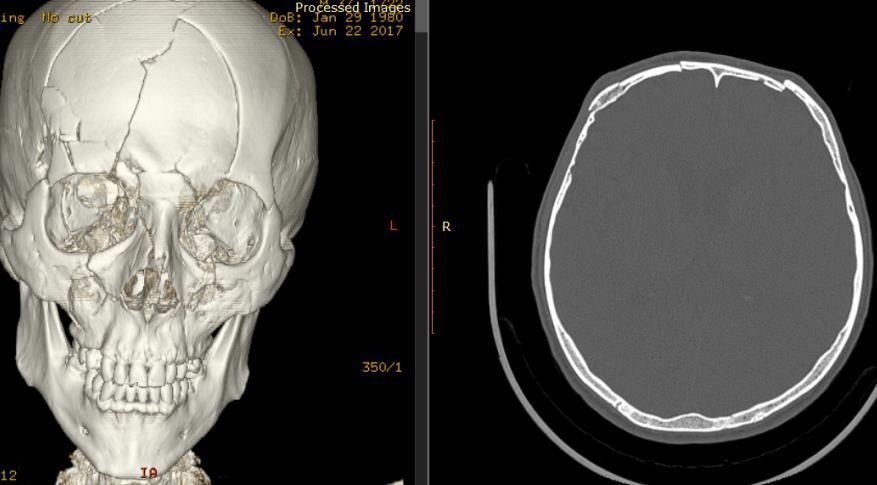

Діагностика

Вдавлений перелом може бути виявлений при хірургічній обробці рани, за допомогою рентгенографії кісток черепа, і краще за все діагностується при виконанні комп’ютерної томографії голови.

Вдавлені переломи стінок лобових пазух

Іноді, при травматичних ушкодженнях лобової кістки, може виникати так званий вдавлений перелом зовнішньої та / або внутрішньої стінок лобової (фронтальної) пазухи.

Вона розташовується в області надбрів’я, є повітроносною пазухою, її стінки є досить тонкими та досить легко ламаються, що проявляється досить помітним вдавлення в травмованій області, яке сприймається як серйозний косметичний недолік.